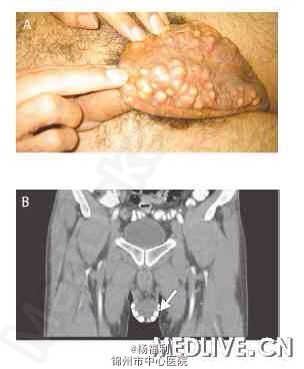

38岁男患。 25年前患者发现双侧阴囊多发性肿物,肿物大小无变化,肿物内容物为皮脂样。一直未给予治疗。今来我科治疗。

查体:双侧阴囊布满多发结节样肿物,质硬。大小约1cm左右。 大体图片:非常遗憾没能照一下,网上找到的图片,就是这样子。(图片来源网络,具体找不到出处,向作者致敬。) 血常规及血糖、尿酸异常。余肾功及离子正常。见图片。 病理:病理形态符合阴囊钙沉着,伴异物巨细胞反应。

诊断:阴囊钙质沉积症 处理;手术切除。